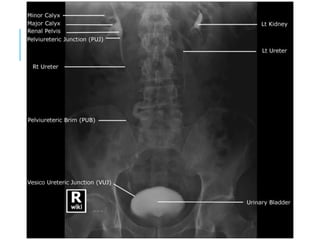

KIDNEY

Anterior: The right kidney lies 1.25 cm lower than

the left.

On the anterior surface, the centre of the hilum lies in

the transpyloric plane 5 cm from the midline and

slightly medial to the tip of the ninth costal cartilage.

From the hilum, the outline of the anterior surface can

be drawn 11 cm long and 4.5 cm broad, the upper pole

being 2.5 cm, and the lower 7.5 cm, from the midline

Posterior- the posterior surface, the centre of the

hilum lies opposite the lower border of the spinous

process of the first lumbar vertebra and 5 cm from the

midline.

The outline of the posterior surface can be traced

similarly to the anterior surface.

The lower pole is 2.5 cm above the summit of the iliac

crest.

The kidneys are 2.5 cm lower in the standing than in

the supine

KIDNEY AND URETERS